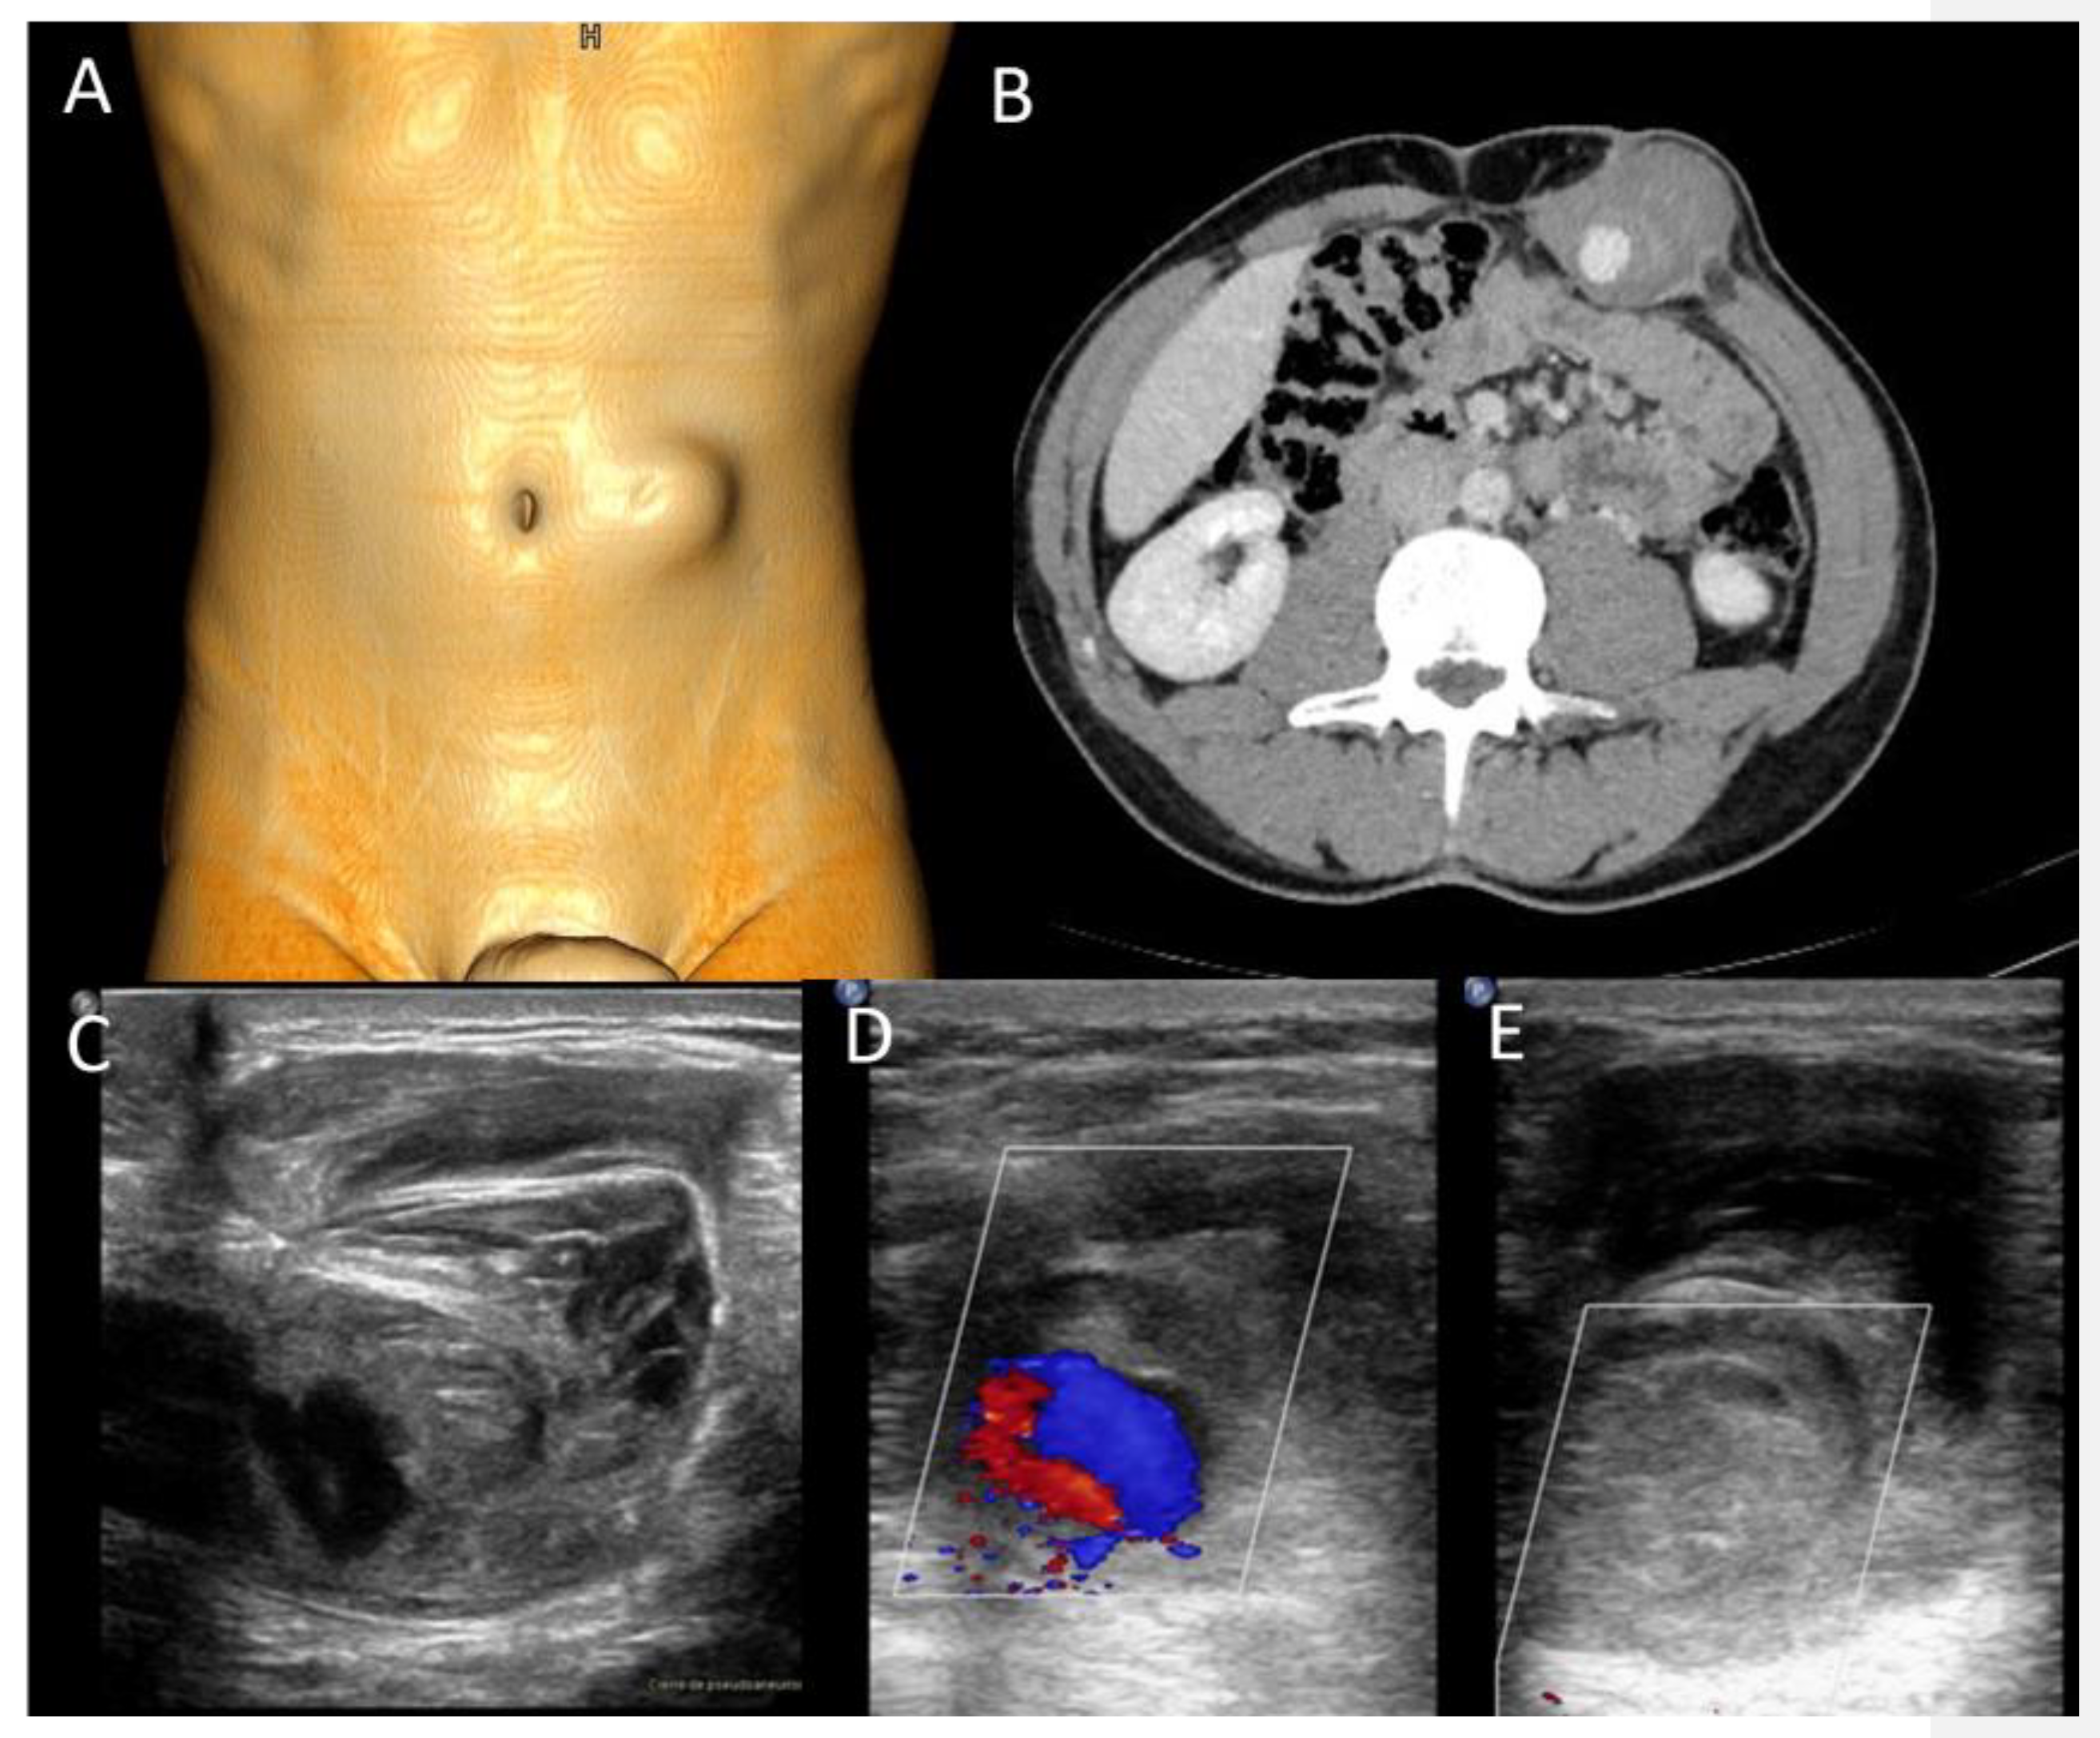

Abdominal wall abscesses present on US as superficial fluid-filled complex lesions, with ill-defined margins, predominantly hypoechoic to surrounding muscles [7,8]. Peripheral hyperemia can be seen on Color Doppler US (CDUS) [3] (Figure 1). To define the extent of the abscess, contrast-enhanced CT and MR could be used in severe cases.

Figure 1. Abscesses on US and CT in a 69-year-old woman with myelofibrosis, presenting with pain along the surgical scar and persistent fever two weeks after splenectomy. B-mode US (first picture, arrow) demonstrates a fluid collection, with no significant vascularization on color Doppler (CD, lower picture). On portal-phase CT (third picture), the abscess is easily distinguishable (arrowhead).